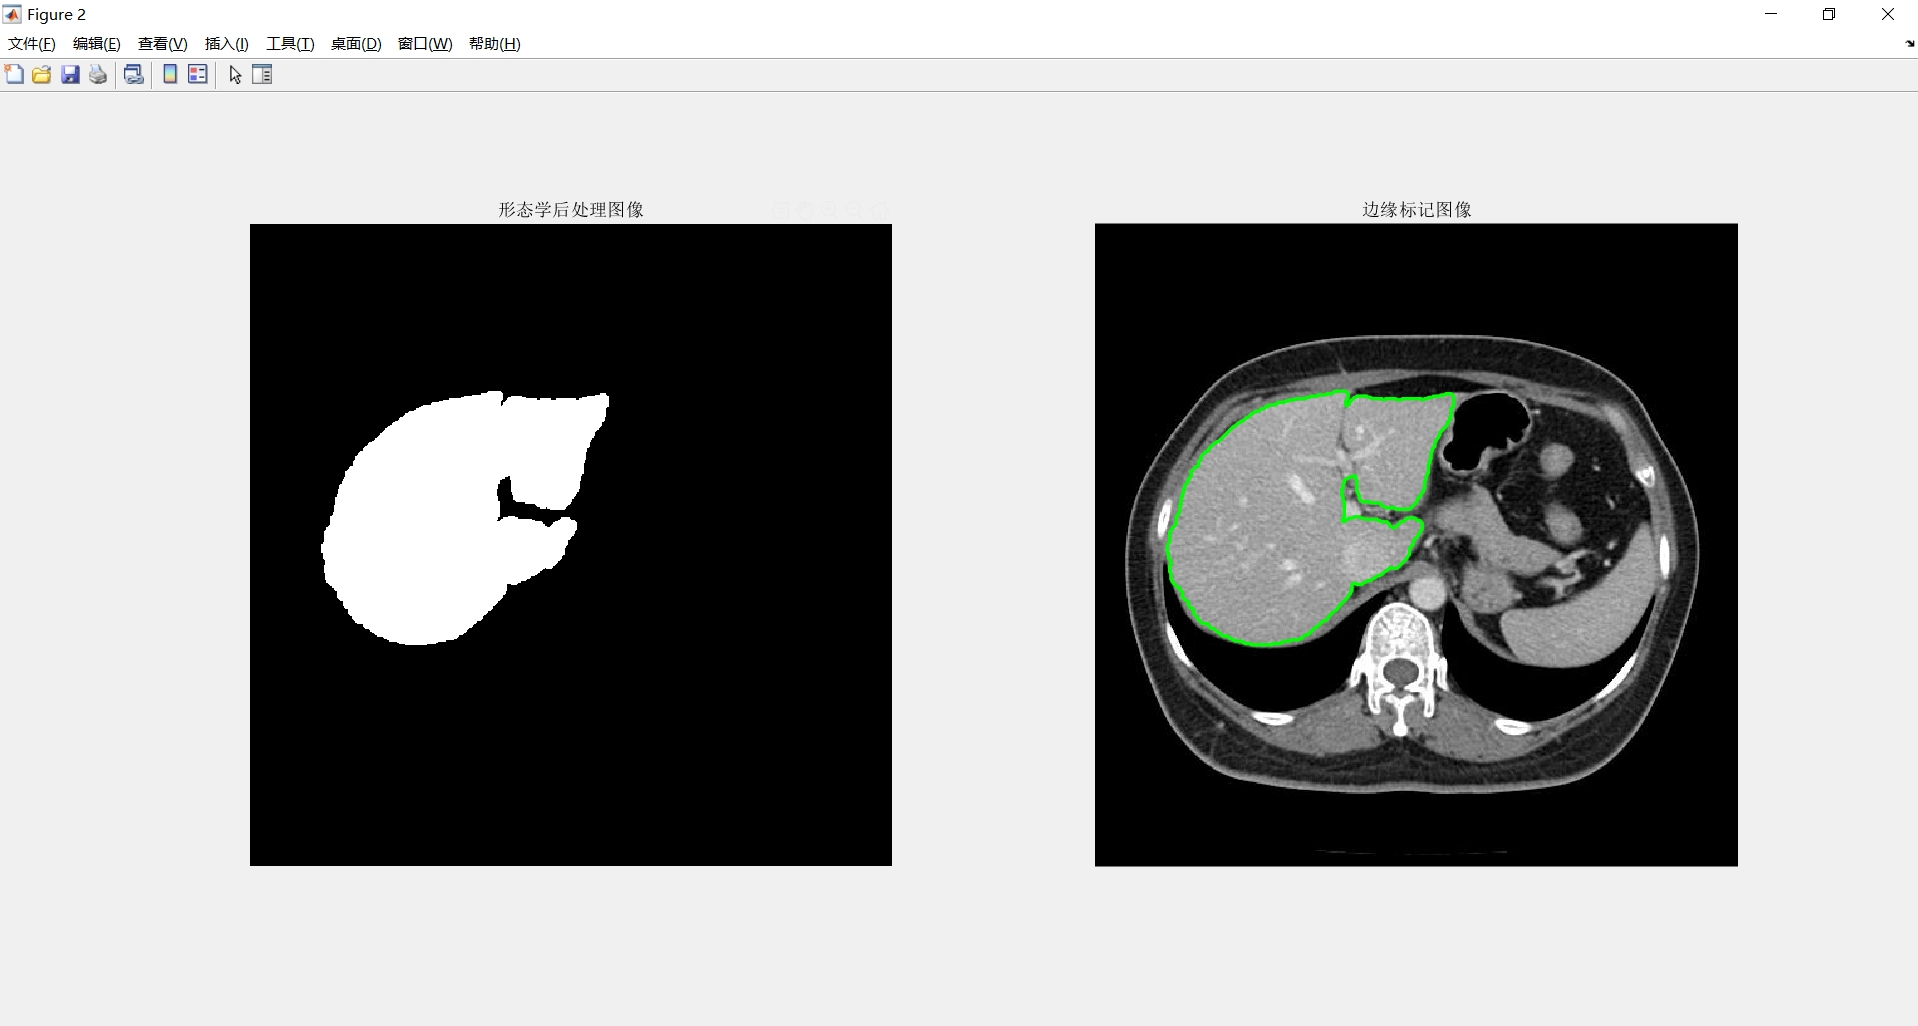

区域生长:它是根据事先定义的准则将像素或者子区域聚合成更大区域的过程。

其基本思想是从一组生长点开始(生长点可以是单个像素,也可以是某个小区域),将与该生长点性质相似的相邻像素或者区域与生长点合并。

然后将这些新像素当作新的生长点,继续上面的操作,一直重复此过程,直到没有满足条件的像素可被包括进来,此时就表示生长点已经不能生长,这样一个区域就生长成了。

生长点和相似区域的相似性判断依据可以是灰度值、纹理、颜色等图像信息。